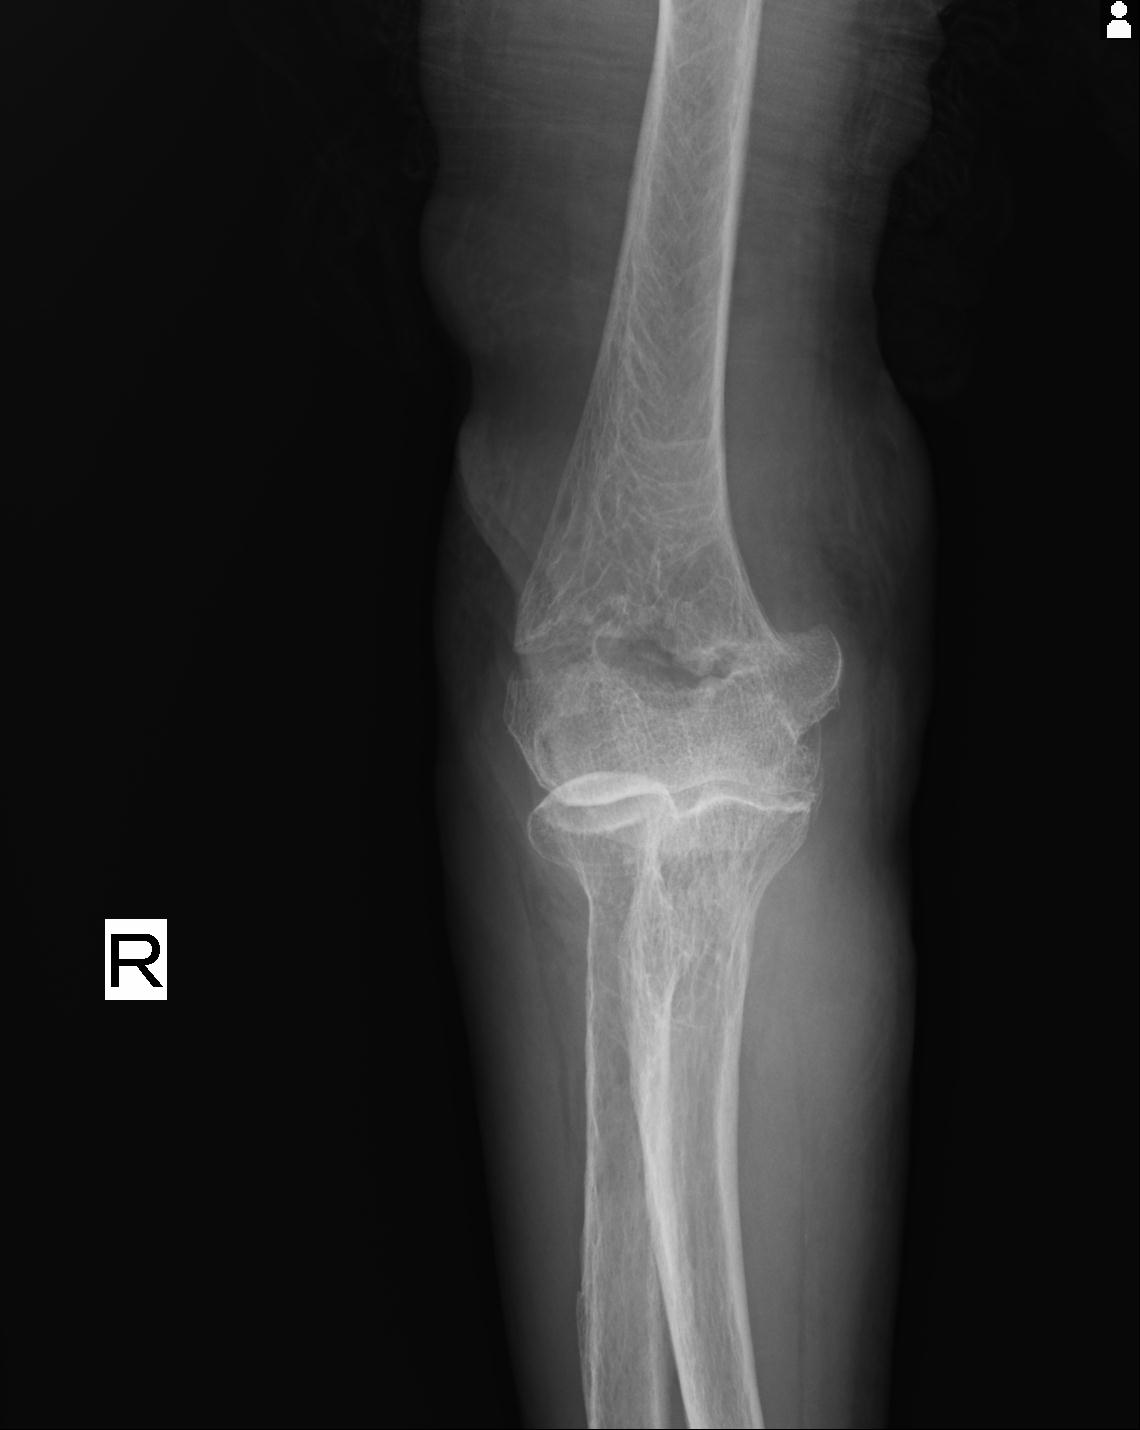

2271 1/25 右肘 4R 1/27 4R 3/24 4R 94歳女性 右通顆骨折